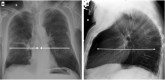

Fig. 9

Chest-X-ray in two projections (postero-anterior and latero-lateral) shows a typical example of lung emphysema with pulmonary hyperinflation, flattened hemidiaphragms, and increased lung (A) and retrosternal (B) radiolucency